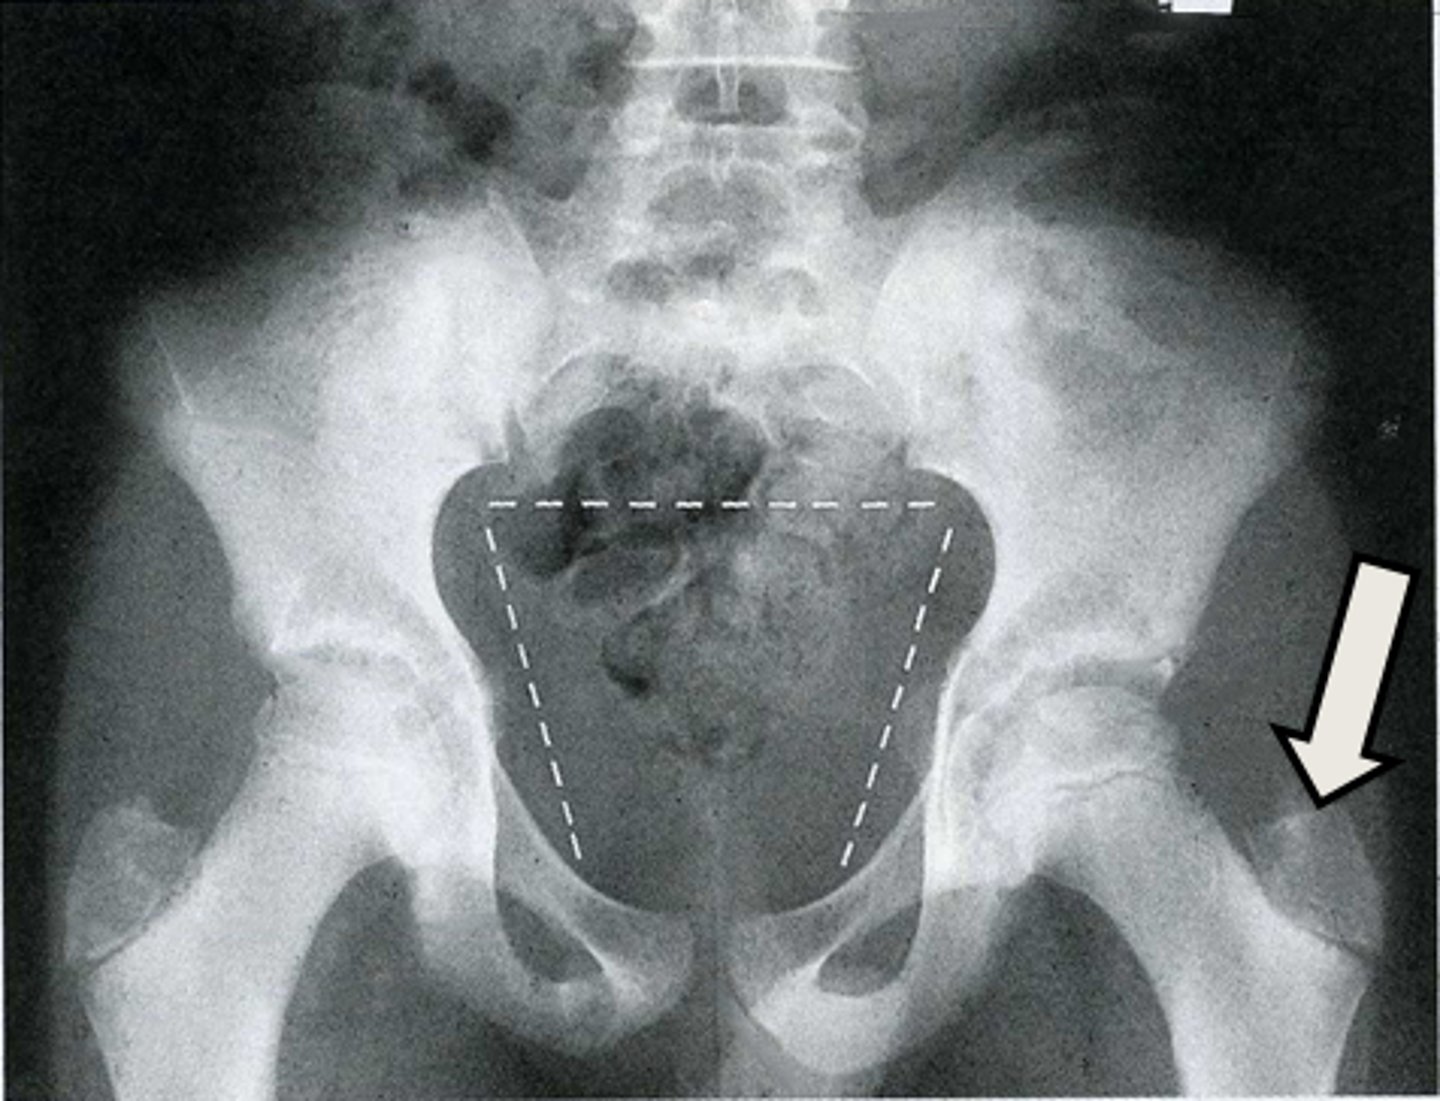

AP pelvis

What is the image?

2

Acetabulum

<p>What is indicated in the image?</p>

New cards

What is indicated in the image?

4

Epiphysial plate

6

Hip joint

8

Ischial spine

10

Nonfused greater trochanter

12

Pubic symphysis

14

Sacrum